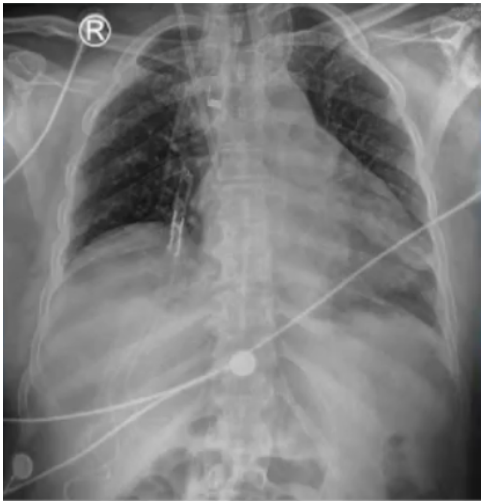

8月19日复查血气分析(呼吸机辅助呼吸,SPONT模式,PSV 18 cmH2O,PEEP 8 cmH2O,氧浓度35%):pH 7.520,PaCO2 56.0 mmHg,PaO2 144.0 mmHg,SaO2 99%。SBT通过,复查支气管镜见气道内少许分泌物,黏膜光滑无肿胀,于8月19日脱机拔管,序贯无创呼吸机辅助呼吸。气管导管尖端培养、灌洗液培养(8月19日送检)均为肺炎克雷伯杆菌;血培养(8月16日送检)为白色念珠菌。血NGS回报金黄色葡萄球菌(序列数3),覆盖度0.01%。继续延用替加环素+多黏菌素B+卡泊芬净的治疗方案。患者8月19日拔管后仍出现反复发热,考虑仍与感染有关。然而,从8月21日胸部X线片可见肺部病变有所好转(图8)。8月22日胸部CT可见两侧胸腔积液明显吸收,双肺实变、渗出灶较前明显好转(图9)。考虑患者发热的原因可能并非肺部感染。8月23日查体见患者背部、腹股沟区、左下肢点片状红疹。考虑可能为药物热所致,遂停用多黏菌素B、替加环素,改为哌拉西林他唑巴坦4.5 g ivgtt q8h抗感染治疗,继续卡泊芬净抗真菌治疗。调整治疗方案后患者最高体温下降,但仍有发热。为了排查感染问题,8月26日拔除PICC管,之后2~3天,患者体温逐渐恢复正常。因此考虑患者可能合并血流感染。之后患者一般情况好转,8月27日复查胸部X线片提示病情进一步好转(图10)。8月29日转入普通病房,后一直未再发热,9月13日出院。